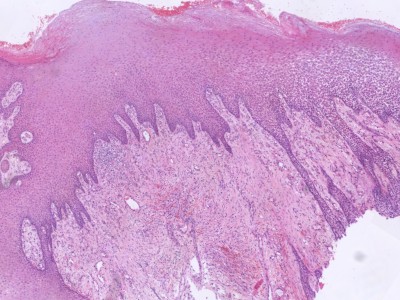

PA:Histologisch beeld varieert nauwelijks

tussen de verschillende subtypen. De histologie is wel afhankelijk van het ziektestadium.

'Patch' stadium: proliferatie van kleine vaten in de oppervlakkige dermis met

een mild infiltraat, bestaande uit lymfocyten en plasmacellen.

'Plaque'

stadium: vasculaire proliferatie tot in de diepe dermis en soms de subcutis.

Spoelcellen (met expressie van endotheelmarkers) nemen de plaats van het

dermale collageen in. Er liggen groepjes erytrocyten buiten de vaten

(erytrocytenextravasatie), en in gedilateerde spleetvormige vaatruimten

('slit-like' ruimten). Het endotheel is gezwollen, er is endotheliale celatypie, en soms is een erytrocyt omsloten door één endotheelcel (erytrocyten phagocytose). Er

is depositie van hemosiderine. Tevens een mononucleair infiltraat (lymfocyten en plasmacellen). Vroege laesies kunnen lijken op granulatieweefsel, met veel, wijde capillairen, grote endotheelcellen, en een diffuus chronisch ontstekingsinfiltraat (lymfocyten, plasmacellen, macrofagen).

Meestal afwezigheid van atypie, mitosen en pleiomorfisme;

komt soms voor in late stadia.

![Histologie Kaposi sarcoom (click on photo to enlarge) [source: Kevin Kwee / Afdeling Pathologie MUMC] Histologie Kaposi sarcoom](../../../pacoupes/thumbnails/Kaposi-sarcoom-1.jpg) |

![Histologie Kaposi sarcoom (click on photo to enlarge) [source: Kevin Kwee / Afdeling Pathologie MUMC] Histologie Kaposi sarcoom](../../../pacoupes/thumbnails/Kaposi-sarcoom-2.jpg) |

|

ingescande coupe (zoom) |

Bron

hoge resolutie PA-foto's: Kevin Kwee en Afdeling Pathologie MUMC. Klik

op de afbeelding om in te zoomen.